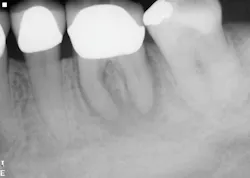

The second case involves a patient with tooth no. 19 having substantial furcation damage and moderate-sized apical periodontitis (figure 3).

Treatment included a two-visit approach, with two weeks in interim calcium hydroxide therapy.

Healing is noted on the six-month follow-up (figure 4).